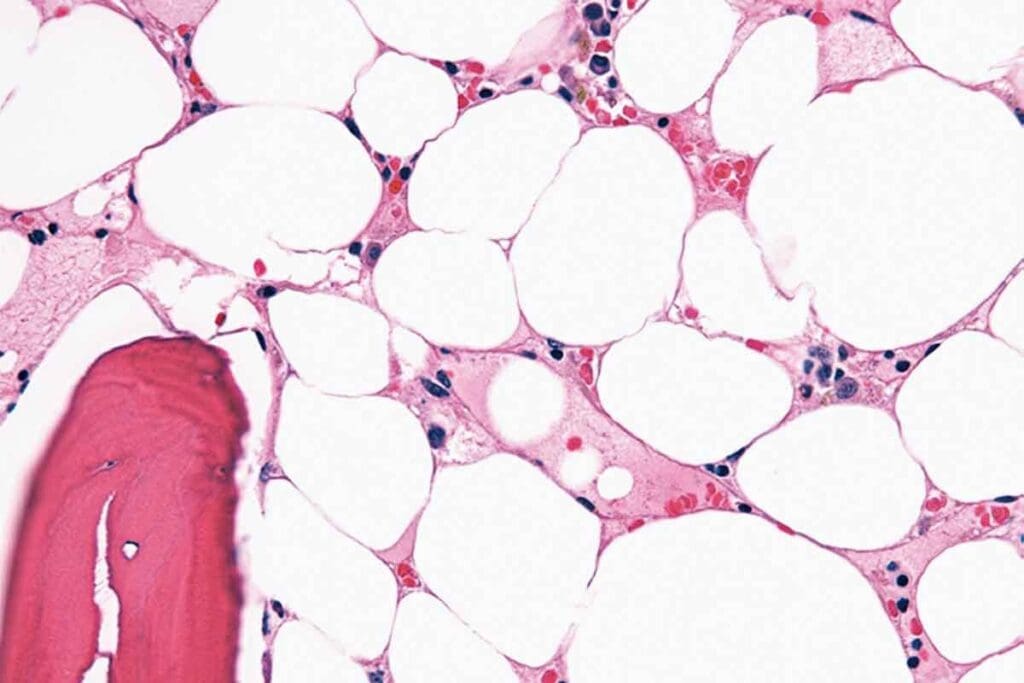

Acute Lymphoblastic Leukemia (ALL) is the most common type of childhood leukemia, making up about 80% of cases. It’s caused by the fast growth of immature lymphocytes, which take over the bone marrow. Thanks to advances in treatment, the acute lymphoblastic leukemia child survival rate has greatly improved.

Acute Myeloid Leukemia (AML) is another type of leukemia that affects children, though it’s less common than ALL. AML is marked by the rapid growth of abnormal myeloid cells in the bone marrow. The childhood acute myeloid leukemia prognosis has also seen improvements, but it’s harder to treat than ALL.